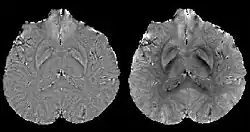

A volume rendered brain QSM acquired at 3 Tesla and reconstructed with morphology enabled dipole inversion (MEDI).

Morphology enabled dipole inversion (MEDI)

A unique advantage of MRI is that it provides not only the phase image but also the magnitude image. In principle, the contrast change, or equivalently the edge, on a magnitude image arises from the underlying change of tissue type, which is the same cause for the change of susceptibility. This observation is translated into mathematics in MEDI,[13] where edges in a QSM which do not exist in the corresponding magnitude image are sparsified by solving a weighted norm minimization problem.[14]

MEDI has also been validated extensively in phantom, in vitro and ex vivo experiments. In an in vivo human brain, MEDI calculated QSM showed similar results compared to COSMOS without statistically significant difference.[15] MEDI only requires a single angle acquisition, so it is a more practical solution to QSM.